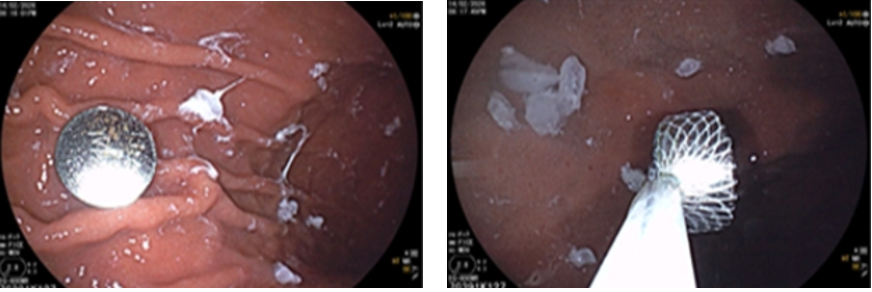

Gia đình phát hiện kịp thời và đưa bé đi khám ngay. Kết quả chụp X-quang phát hiện dị vật trong ổ bụng.

Nội soi dạ dày xác định pin trong dạ dày và đã lấy ra an toàn